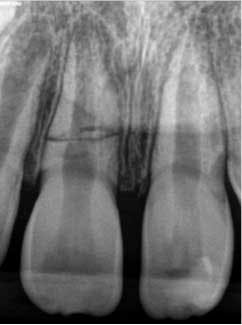

At three months, the clinical testing was equivalent and radiographs showed a fracture still present, but the periodontal ligament (PDL) and lamina dura (LD) were intact and uniform, especially near the fracture line (figure 2). At six months, there was no change in the response to vitality testing and radiographs continued to show no deleterious changes (figure 3).